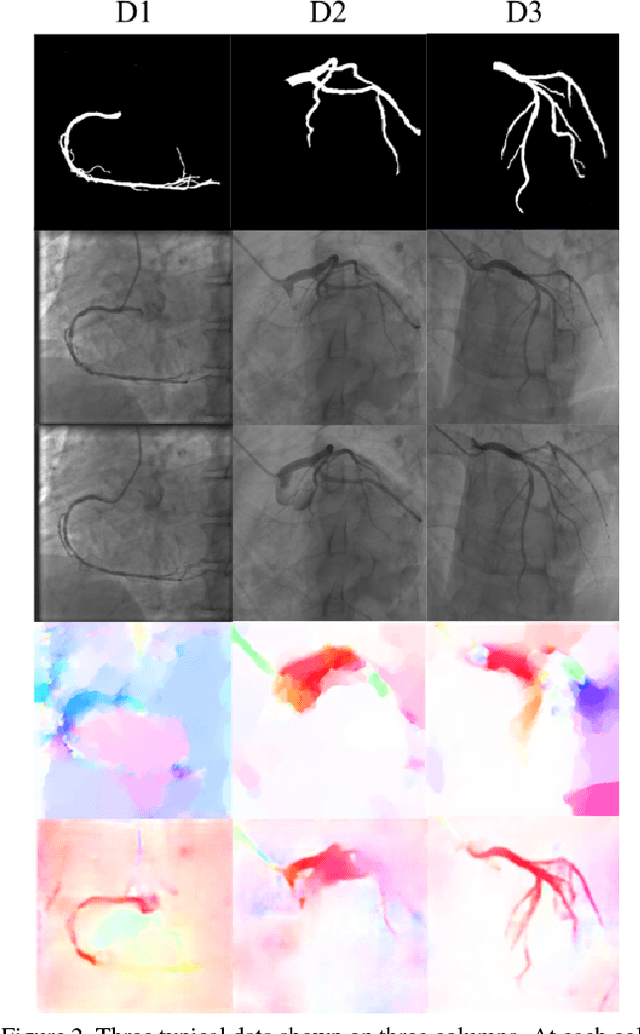

We propose a new self-supervised approach to image feature learning from motion cue. This new approach leverages recent advances in deep learning in two directions: 1) the success of training deep neural network in estimating optical flow in real data using synthetic flow data; and 2) emerging work in learning image features from motion cues, such as optical flow. Building on these, we demonstrate that image features can be learned in self-supervision by first training an optical flow estimator with synthetic flow data, and then learning image features from the estimated flows in real motion data. We demonstrate and evaluate this approach on an image segmentation task. Using the learned image feature representation, the network performs significantly better than the ones trained from scratch in few-shot segmentation tasks.